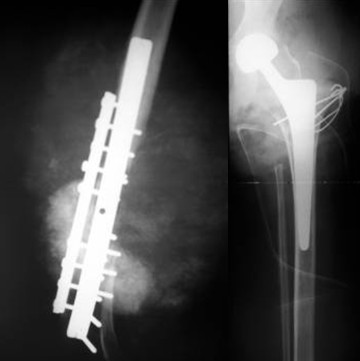

Bei ihr wurde im Herbst 11 ein bösartiger Knochentumor im linken Schienbein entdeckt Die anschliessende Chemotherapie griff ihr Herz so stark an, dass man Carina im September 12 an ein. Endgültig zeigt ein Röntgenbild die typischen Veränderungen durch einen Knochentumor Bestehen Zweifel, ob es sich um gut oder bösartige Tumoren handelt, sind zusätzliche Untersuchungen notwendig, zum Beispiel eine Computertomographie ( CT ) oder eine Magnetresonanztomographie ( MRT ). An artificial knee joint has one part of a femur for attaching to the distal part of a femur and a tibia part for attaching to the proximal part of a tibia The femur is made of aluminium oxide, aluminium dioxide ceramic, zirconium oxide or zirconium dioxide ceramic;.

Gutartige Knochentumoren unterscheiden sich in Ätiologie, Pathogenese und Pathophysiologie Angesichts der zeitlichen Assoziation zum physiologischen Knochenwachstum ist anzunehmen, dass ihr Wachstum durch die gleichen Prozesse mit beeinflusst wird Die meisten benignen Knochentumoren treten sporadisch auf, einige wenige auf dem Boden genetisch bedingter Prädispositionen (z B hereditäre. Ein Knochentumor ist eine Gewebemasse, die sich formt, wenn sich die knochenbildenden Zellen unkontrolliert teilen Eine wachsende Masse kann das gesunde Gewebe durch ein abnormes schwächeres Gewebe ersetzen Der Knochentumor kann verursachen einen Bruch der Knochenbälkchen (Trabekel), aus denen das Knocheninnere besteht, eine Fraktur. Endgültig zeigt ein Röntgenbild die typischen Veränderungen durch einen Knochentumor Bestehen Zweifel, ob es sich um gut oder bösartige Tumoren handelt, sind zusätzliche Untersuchungen notwendig, zum Beispiel eine Computertomographie ( CT ) oder eine Magnetresonanztomographie ( MRT ).